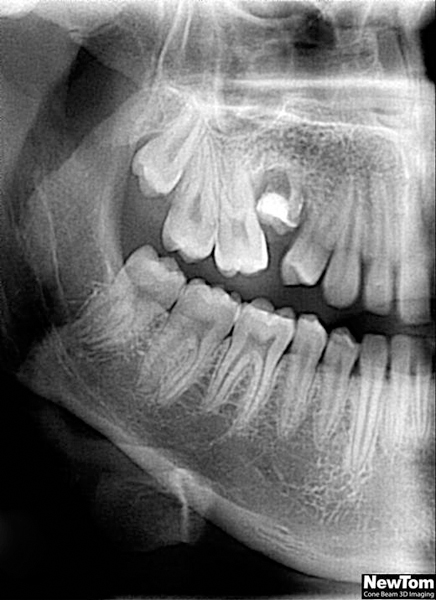

3D DVT - NewTom

Je speciální zubní digitální tříprostorový tomograf (3D), který umožňuje na základě jediného

snímkování vytvořit všechny typy RTG zobrazení, které jsou pro lékaře potřebné. Díky používané technologii tzv. „kuželového paprsku“ a speciálním senzorům je

výrazně zmenšená dávka záření - o více jak 80% proti klasickému CT vyšetření. To je významné zejména u dětí. Pomocí tohoto přístroje je možné zjisti skutečnou situaci v čelistních kostech pacienta tedy množství kosti - můžeme změřit skutečnou šířku i výšku kosti, i kvalitu kosti (hustotu) v místě uvažované implantace. 3D (tříprostorové) zobrazení umožňuje zvýšit prostorovou představu operatéra ještě před vlastní operací a zároveň pacientovi lépe objasnit a ukázat oblast plánovaného zavedení implantátu.

Pacient „neumí číst“ RTG snímky, ale díky 3D zobrazení vidí „svoji skutečnou čelist“

- např. jak je nízká či úzká, vidí průběh nervu nebo velikost čelistní dutiny, což mu umožní i pochopení nutnosti v některých případech provést pomocné zákroky ještě před vlastním zavedením implantátu (viz. kostní štěp, sinus lift, kostní granulát...).

Vyšetření pomocí tohoto přístroje používáme i ve stomatochirurgii (zlomeniny čelistí, zuby moudrosti, cysty, onemocnění čelistního kloubu), ortodoncii (retinované zuby, nadpočetné zuby), parodontologii atd.